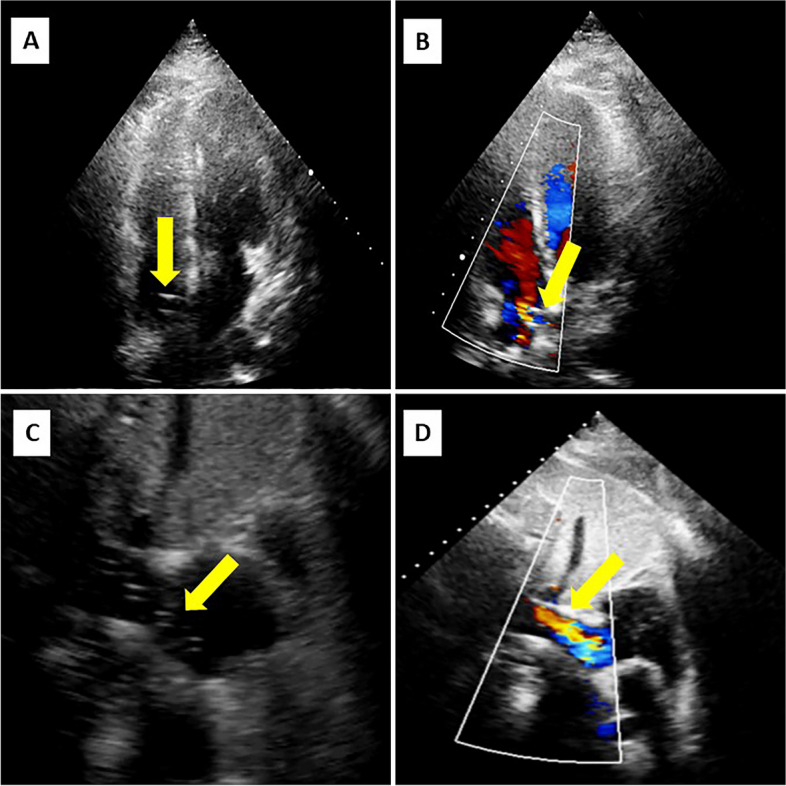

Aims: To evaluate the feasibility of a transthoracic echocardiogram using an apical-subcostal protocol in invasive mechanical ventilation (IMV) and prone position.

Methods: Prospective study of adults who required a prone position during IMV. A pillow was placed only under the left hemithorax in the prone position to elevate and ease the apical and subcostal windows. A critical care cardiologist (prone group) acquired and evaluated the images using the apical-subcostal protocol. Besides, we used ambulatory echocardiograms performed as a comparative group (supine group).

Results: 86 patients were included, 43 in the prone and 43 in the supine. In the prone group, the indication to perform an echocardiogram was hemodynamic monitoring. All patients were ventilated with protective parameters, and the mean end-expiratory pressure was 10.6 cmH2O. The protocol was performed entirely in 42 of 43 patients in the prone group because one patient did not have any acoustic window. In the 43 patients in the prone group analyzed and compared to the supine group, global biventricular function was assessed in 97.7% (p = 1.0), severe heart valve disease in 88.4% (p = 0.055), ruled out of the presence of pulmonary hypertension in 76.7% (p = 0.80), pericardial effusion in 93% (p = 0.12), and volume status by inferior vena cava in 93% (p = 0.48). Comparing prone versus supine position, a statistical difference was found when evaluating the left ventricle apical 2-chamber view (65.1 versus 100%, p < 0.01) and its segmental function (53.4 versus 100%, p < 0.01).

Conclusion: The echocardiogram using an apical-subcostal protocol is feasible in patients in the IMV and prone position.